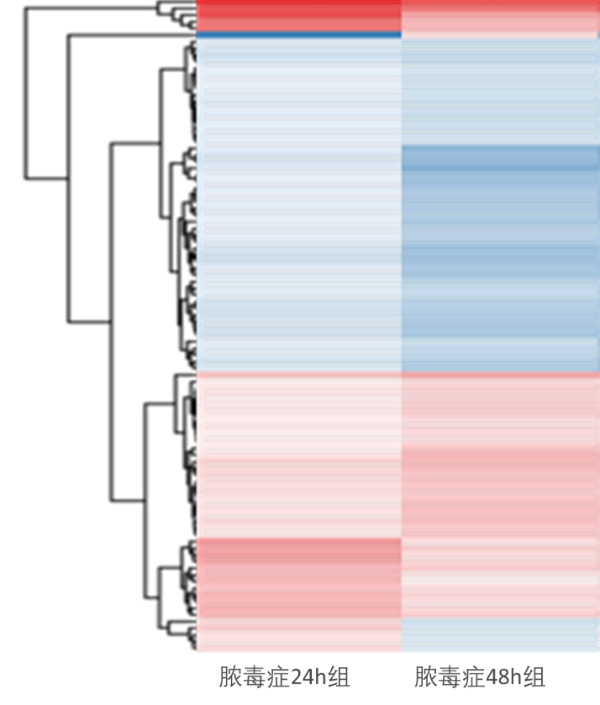

2 结果48 h各组病理结果,对照组脾组织结构正常(见图 1A )。脓毒症组脾组织见白髓结构破坏,红白髓交界模糊,多量组织细胞浸润,红髓充血(见图 1B)。差异mRNA的Volcano-plot分布图(见图 2)。相比于对照组,24 h时脓毒症组脾组织mRNA表达上调的有1 030个,下调的有935个[5];48 h组表达上调的有1 354个,下调的有1 763个。差异mRNA的聚类情况(见图 3)。GO功能分类结果(见图 4)。脓毒症大鼠脾组织部分通路相关基因表达情况(见图 5、6):脓毒症大鼠24 h,48 h脾组织关于细胞因子及其受体相互作用通路相关基因的分布图(见图 7,图 8)。脓毒症大鼠24 h,48 h脾组织关于细胞凋亡相关通路的基因分布图(见图 9,图 10)。

| Y轴:差异基因。颜色:差异倍数(红色:↑,蓝色:↓,颜色越深倍数越大) 图 3 差异mRNA聚类情况 |

早期过度炎症反应、晚期免疫抑制系脓毒症的重要机制之一[6-7]。脾脏为人体免疫器官,在血源性抗原出现时,负责启动免疫反应[9]。脓毒症时SIRS反应可引起脾功能障碍[10]。本研究发现脓毒症48 h大鼠脾组织白髓结构破坏,红白髓交界模糊,其结构改变可能影响其免疫功能。既往对脓毒症大鼠24 h采用基因芯片分析发现部分基因表达异常[11]。若能进一步研究其早晚期的相关基因表达变化也许对脓毒症脾功能障碍有进一步的诠释。本研究采用RNA-seq技术对脓毒症大鼠早晚期脾组织行mRNA检测,是既往研究的深入,发现脓毒症早期组脾组织基因上下调数远少于晚期组,如脓毒症24 h组脾组织mRNA上调数1 030个,下调数935个,而48 h组mRNA上调数1 354个,下调数1 763个,差异明显(见图 2),符合疾病的发展过程。从图 3看,脓毒症24 h、48 h部分区域从红色趋于变浅甚至变蓝,浅蓝趋于蓝色,直观的反应脓毒症时脾脏基因表达量变化情况。从GO功能分类结果(图 4)得知,cellular processes、Environmental informationProcessing、Genetic Information Processing、Human Diseases、Metabolism、Organismal Systems相关功能基因随时间发展出现差异表达数为上升趋势。进而我们对其分析发现,脓毒症早晚期脾mRNA出现变化主要涉及细胞因子与其受体相互作用、IL-17、T细胞受体、TH1、TH2细胞分化、TNF、Toll受体、凋亡等相关信号通路。研究显示,脓毒症晚期免疫抑制可能是脓毒症患者死亡的主要原因,免疫治疗可能是未来一大趋势[12-15]。本文拟从炎症反应与细胞凋亡相关通路来阐述脓毒症脾功能障碍的相关机制。